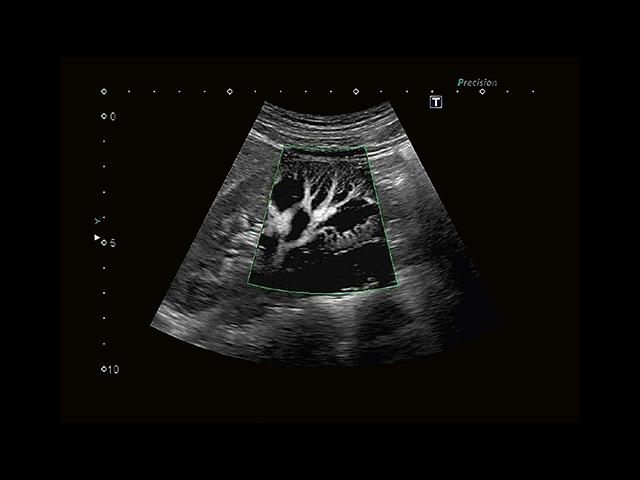

Обновленная версия легендарного УЗ-сканера. Стационарный аппарат экспертного класса Aplio 500 Toshiba NEW, визуализирует анатомические структуры в высоком разрешении. Модель позволяет выявить микрокальцификаты, новообразования, нарушения в работе сердца, сосудов и мышц. Присутствует функция виртуальной эндоскопии, 4D-сканирования, эластометрии тканей, УЗИ с контрастированием. За повышение качества изображения отвечают технологии ApliPure и Superb Microvascular Imaging. Первая задействует возможности пространственного и частотного кодирования, формирует цельный визуальный ряд с сохранением клинических маркеров. Вторая улучшает отображение микрососудистого русла, используя доплеровский эффект. Модель оснащена 21-дюймовым монитором, имеет 4 активных порта. Возможно подключение педиатрических, интраоперационных, лапароскопических и чреспищеводных датчиков.

• Fly Thru. Виртуальная эндосонография обеспечивает построение трехмерной модели полостей, протоков и сосудов в рельном времени, облегчает организацию инвазивных процедур и динамических исследований. Посредством Fly Thru можно установить шунты и стенты, проводить точные оперативные вмешательства.

Общая визуализация, Гинекология и акушерство, УЗИ для кардиологии